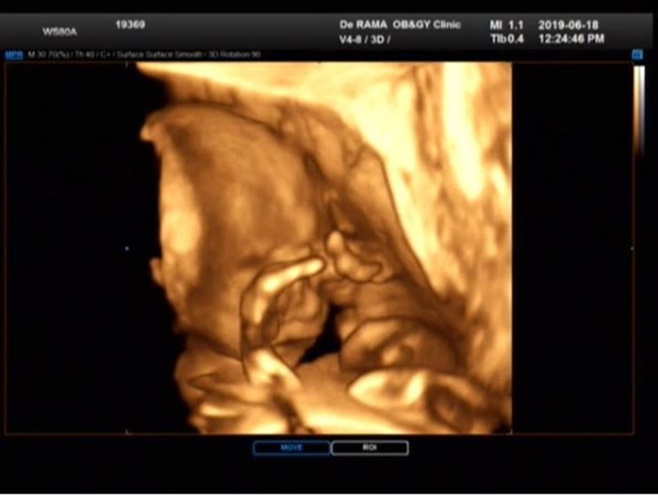

Á¤¾Æ´Â 19ÀÏ ¿ÀÈÄ SNS¿¡ "¿ì¸® ²Üº¹ÀÌ ´« ºñºñ°í ÀÖ¾î¿ä. ¾ö¸¶´Â ¾ó±¼ ´Ù º¸°í½ÍÀºµ¥ ºÎ²ô·¯¿î °Å´Ï? ±Í¿©¿ö ¹ÌÄ¡°Ú³× ¾ÆÁÖ ±×³É #21ÁÖ#²Üº¹ÀÌ#ÀÔüÃÊÀ½ÆÄ#ºÎ²ô·³ÀïÀÌ"¶ó´Â ±Û°ú ÇÔ²² ÇÑ ÀåÀÇ »çÁøÀ» °ÔÀçÇß´Ù.

°ø°³µÈ »çÁøÀº žÆÀÇ ¸ð½ÀÀÌ ´ã±ä ÀÔü ÃÊÀ½ÆÄ »çÁøÀÌ´Ù. Á¤¾Æ´Â ¾ÆÀÌÀÇ ¸ð½ÀÀÌ ¶Ñ·ÇÇÑ »çÁøÀ» º¸°í "±Í¿©¿ö ¹ÌÄ¡°Ú´Ù"¸ç ±â»ÝÀ» Ç¥Çß´Ù.